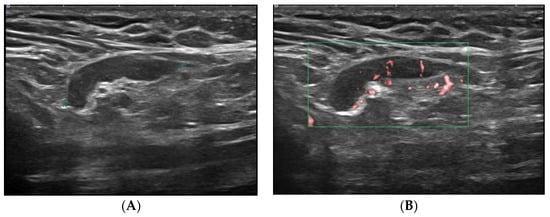

- Cocco, G.; Delli Pizzi, A.; Fabiani, S.; Cocco, N.; Boccatonda, A.; Frisone, A.; Scarano, S.; Shiavone, C. Lymphadenopathy after the anti-COVID-19 Vaccine: Multiparametric ultrasound findings. Biology 2021, 10, 652. [Google Scholar] [CrossRef]

- Granata, V.; Fusco, R.; Setola, S.V.; Galdiero, R.; Picone, C.; Izzo, F.; D’Aniello, R.; Miele, V.; Grassi, R.; Grassi, R.; et al. Lymphadenopathy after BNT162b2 Covid-19 vaccine: Preliminary ultrasound findings. Biology 2021, 10, 214. [Google Scholar] [CrossRef]